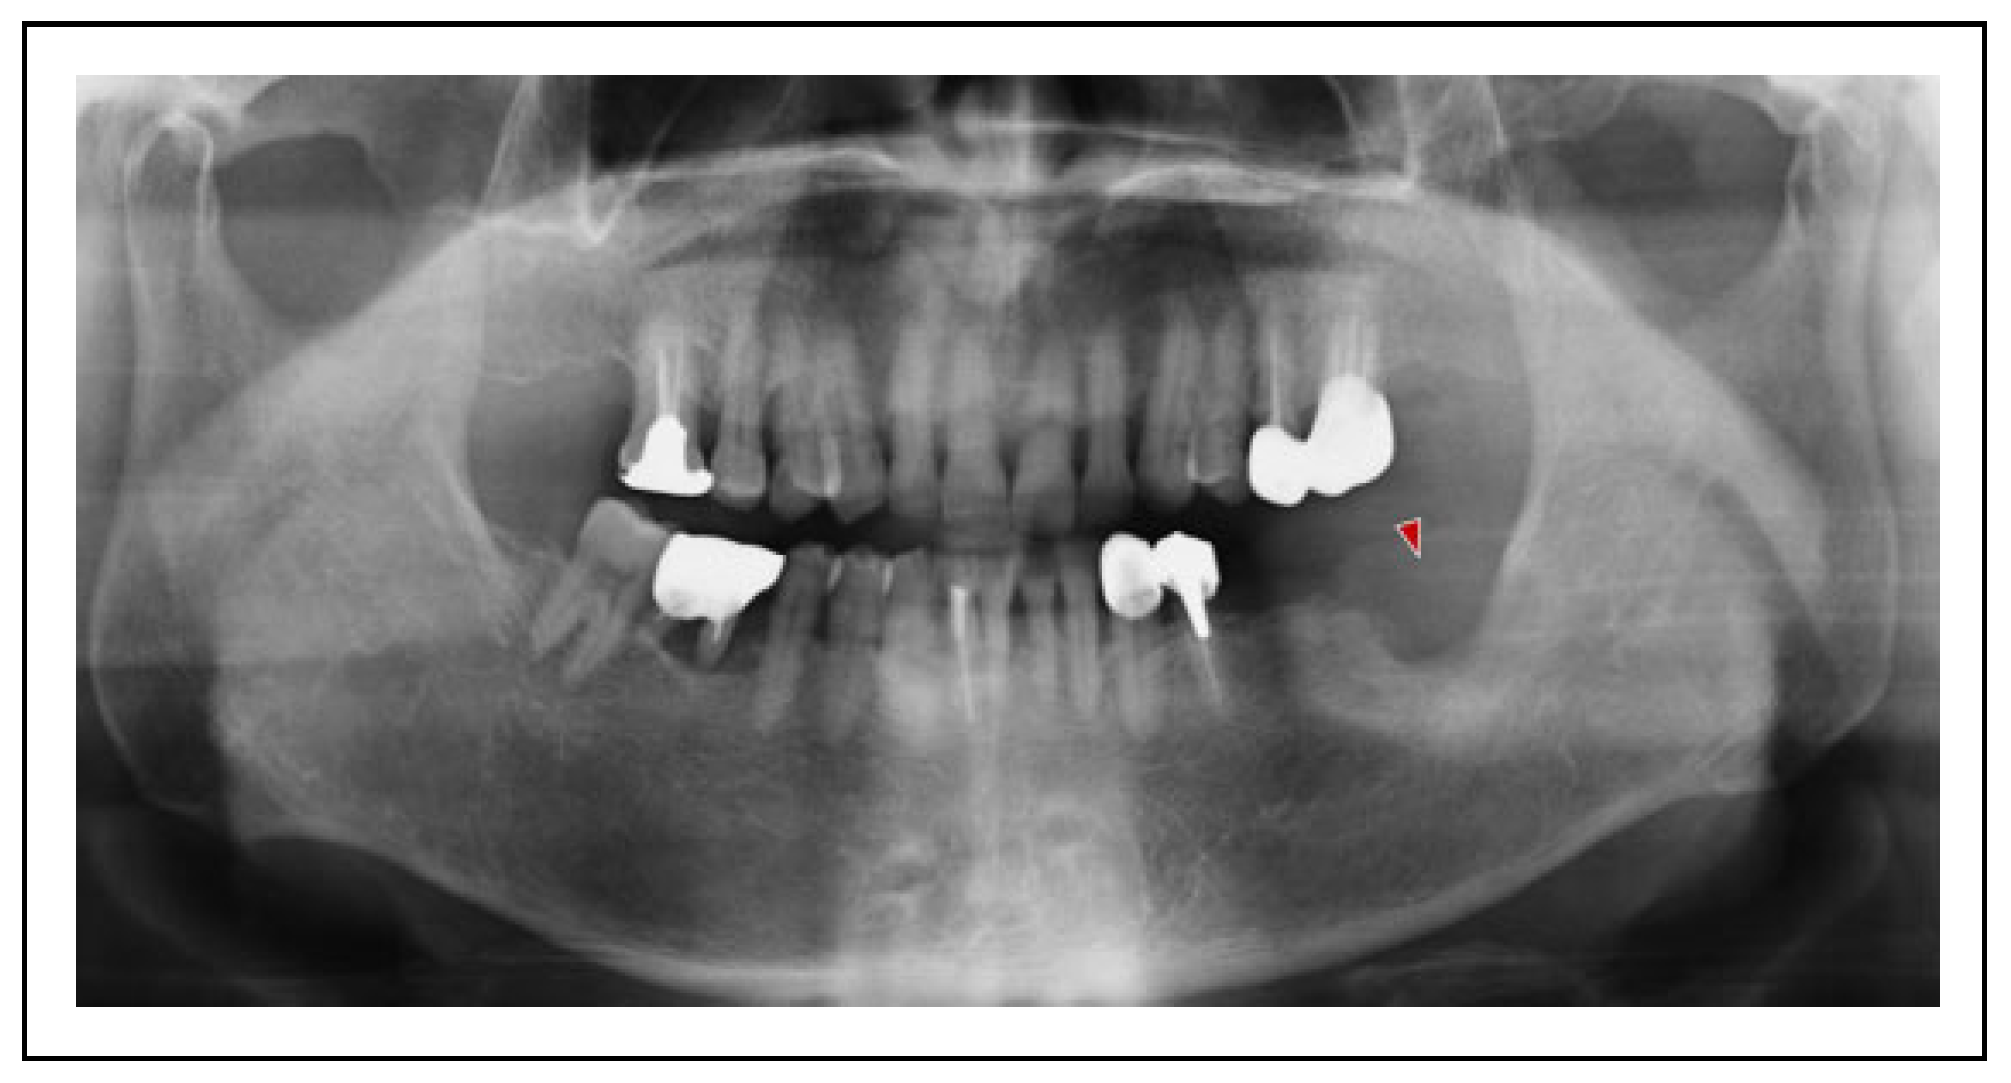

Case Presentation

Surgical Procedure